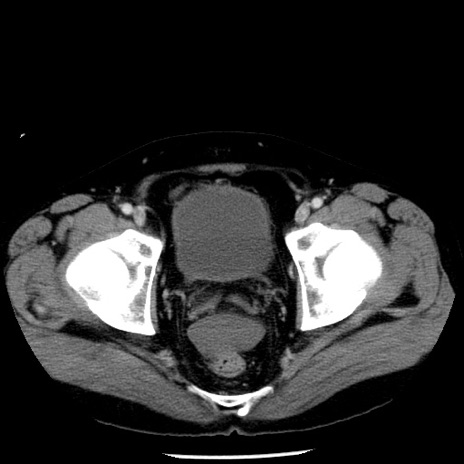

症例29(横断像)

【症例】40歳代男性

【現病歴】2日前から胃痛あり。徐々に周期的な激痛に変化した。本日になっても激痛があるため受診。

【身体所見】意識清明、BT 38-39℃台あり、腹部:膨満、やや硬、右下腹部に圧痛あり。

【データ】WBC 8500、CRP 23.26